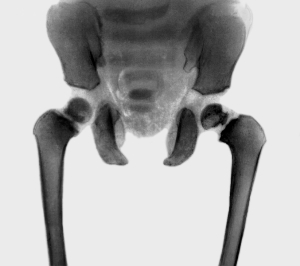

При подозрении на подобное состояние применяется УЗИ, которое безопасно для новорожденного и является эффективным диагностическим способом для выявления ядер в головке бедренной кости и оценивания двигательных функций.

При сомнении используют рентгенисследование (прямая проекция).